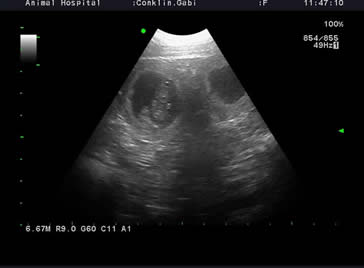

This page will be updated weekly once puppies are born. Gabi is expecting at least 7 puppies to arrive around March 11-13th. Her pregnancy was confirmed with 2 ultrasounds, and xray due March 6th to confirm how many pups to expect. I will post puppy pictures a few days after birth for it takes much devotion making sure puppies in neonatal stages survive as well as all the attention to Gabi too. Be patient for additional information will be coming.

X-rays taken March 6, 2020 showing approximately 7 pups (sorry web images only for displaying size)